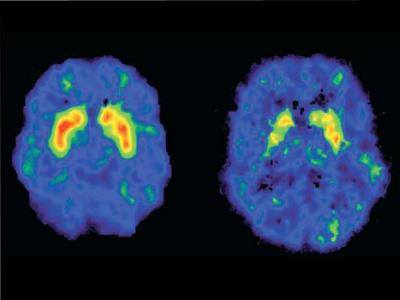

Ya sea inyectada o inhalada, se convierte en morfina al llegar al cerebro. Allí, se adhiere a los receptores opiáceos del tronco del encéfalo y de las zonas rela­cionadas con la percepción del dolor. El consumidor entra en un estado de sopor en el que desaparece to­do tipo de dolor físico y mental. También provoca una caída de los niveles de oxígeno cerebral, lo que causa daños irreparables. Esto explica la debilidad, temblo­res, espasmos y, en casos extremos, infarto cerebral y el párkinson propios de los heroinómanos.Imagen: cerebro sano (izquierda) vs. cerebro de una persona con adicción a la metanfetamina (derecha). Instituto Nacional de Abuso de Drogras (NIDA).